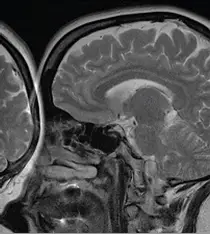

腦部的磁振影像如下圖,出現了後腦勺干擾腦部的影像,若要消除此一干擾,應如何修改掃描參數?

觀察題目提供的腦部磁振造影(MRI)矢狀切面(Sagittal view,為 T2-weighted image)影像,可以發現一個非常明顯的異常:在影像的左側(病人臉部前方、額頭與鼻子前方),出現了原本應該位於病人後腦勺(枕部,occipital region)的腦組織與頭骨影像。這種解剖構造超出影像邊界後,從另一側「摺疊」重疊進入畫面中的現象,是極為典型的反摺假影(Wrap-around / Aliasing artifact)。

本題影像明確展示了後腦區域的組織訊號反摺疊加到臉部前方的現象,即反摺假影(Aliasing artifact)。在 MRI 的空間編碼中,依據奈奎斯特理論(Nyquist theorem),若取樣率不足以涵蓋整個受測物體(即 FOV 設定過小),視野外的訊號就會被錯誤對應到對側。由於頻率編碼(Frequency encoding)方向可以輕易透過硬體濾波器(Oversampling / Low-pass filter)消除視野外的訊號,因此現代 MRI 的反摺假影幾乎都發生在相位編碼(Phase encoding)方向。